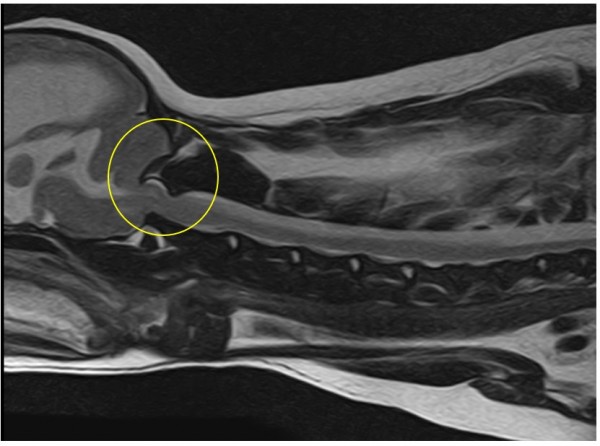

① 환축추 아탈구 (Atlantoaxial Instability, AAI)

- 제1경추(atlas) 와 제2경추(atlas) 사이의 간격이 넓어짐

- 치아돌기(dens) 변위로 인한 척수 압박 유발

- 횡인대와 익인대가 비정상적이거나 관찰되지 않아, 선천적 인대형성 이상 또는 파열 의심

- 척수 내 presyrinx(부종) 및 syringomyelia(척수 공동증) 소견이 나타남

- 이외에도 C2 부위의 dural band와 일부 경추 디스크 퇴행성 변화가 확인됨

② 뇌 기형 및 수두증

- 후두골 기형(Occipital malformation) 으로 인해 소뇌 압박

- 연수의 구부러짐 (medullary kinking) 및 CSF 흐름 장애 발생

- 제1경추의 후방 구조가 두개골과 겹치는 atlanto-occipital overlapping(AOO) 소견도 동반되어,

- 추가적인 뇌압박이 유발

- 뇌실 확장(ventriculomegaly) 및 선천성 수두증(hydrocephalus) 확인

- 다수의 두개골 결손(calvarial defects) 도 관찰되었으나, 뇌 탈출은 없는 상태